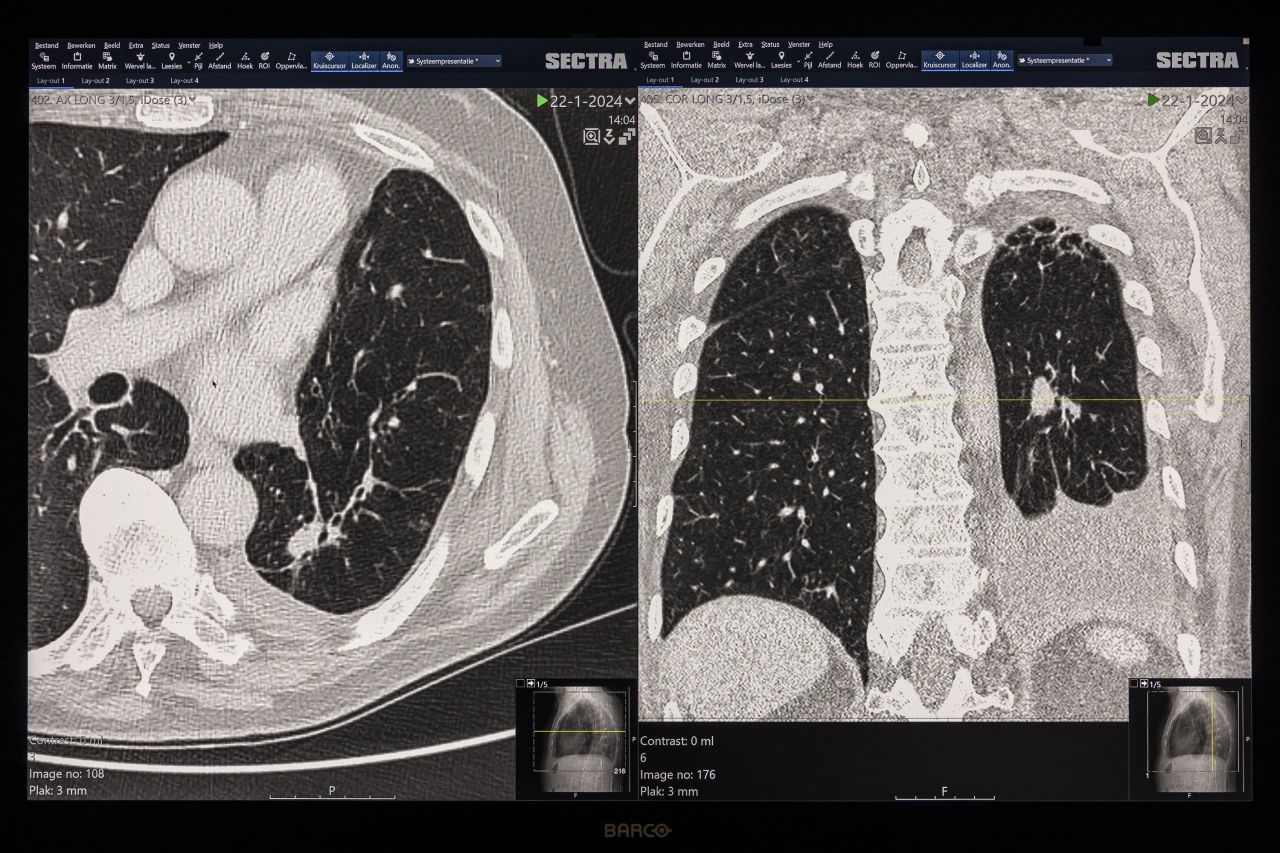

De afdeling radiologie zet Veyelung in als pilot bij patiënten die gescand en vervolgd worden voor het hebben van een of meerdere longnodules. Dat is een groep van zo’n 300 tot 400 patiënten per jaar. Radioloog Ivo van den Elskamp: “Beginnende longtumoren wordt op scans zichtbaar als kleine bolletjes, of nodules. Op scans zijn longen zwart en die bolletjes wit. Dat contrast is groot. Om te weten of het kanker is, worden bij deze patiënten op meerdere momenten CT-scans gemaakt. Er zijn namelijk meer zaken in de longen zichtbaar als kleine bolletjes. Bijvoorbeeld sarcoïdose. Ook na een infectie blijven er bolletjes zichtbaar. Maar die bolletjes groeien niet. Om te weten wat voor bolletjes het zijn, is dus follow-up onderzoek nodig. Na een paar maanden maak je dan weer een scan en kijk je of die bolletjes groeien. Zo vis je de tumoren eruit.”

Dat detecteren van die bolletjes deden de radiologen door met het blote oog alle CT-scans na te kijken. Van den Elskamp: “CT-onderzoek levert een stapel beelden op van telkens een ander ‘plakje’ van de longen. Wij controleren plakje voor plakje en dat duurt wel even. Maar met deze software van Veyelung gaat het automatisch en ook veel sneller. Wij slaan CT-beelden op in ons eigen PACS-systeem, ons beeldarchief. Van daaruit sturen we de beelden naar Aidence. Aidence analyseert de scan met hun AI-software en stuurt de beelden terug naar ons archief met een soort overlay waarop de nodules duidelijk gemarkeerd zijn. We zien direct waar de bolletjes zitten.”